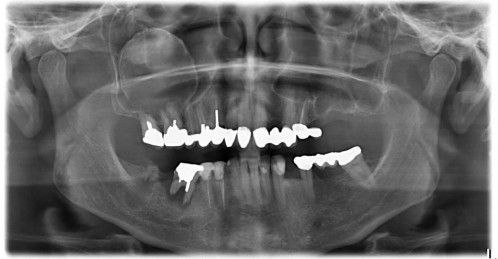

45-jähriger Patient stellt sich erstmalig bei Ihnen in der Praxis vor. Er berichtet, seit 4 Jahren nicht mehr beim Zahnarzt gewesen zu sein, da er keine Zahnschmerzen gehabt habe. Jetzt möchte er zur Prophylaxe kommen.

Allgemeinerkrankungen liegen, soweit er weiß, nicht vor. Die Frage nach Medikamenteneinnahme verneint er.